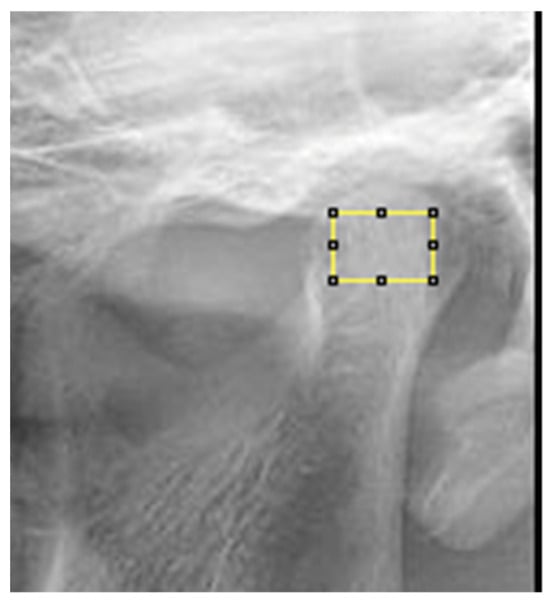

- Defining the region of interest (ROI: region of interest): condylar process, subcortical area of the condyle for OPTs (Figure 6);